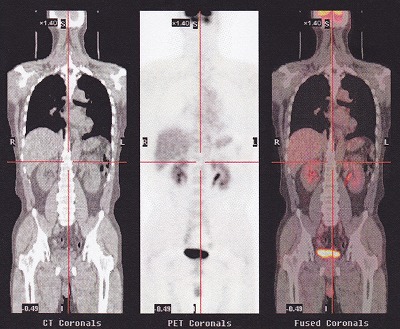

PET-CT検査と呼ばれているものです。

陽電子放射断層撮影装置のことで、ポジトロン・エミッション・トモグラフィー[PositronEmissionTomography]の略語です。X線CTのような形をした「カメラ」を用いて全身や心臓、脳などにおいて、病気の原因や病巣、病状を的確に診断する新しい検査法です。

この、細胞が取り込んでいる隙に、撮影すると、おおく取り込んでいる部分が赤く光る!この検査は、がん細胞が、自分から光ってくれる。。

ただし、尿となって流れ出すので、肝臓、腎臓、そして終着点の膀胱は真っ赤に光る。

口周りや、脳も活発に活動しているので、多く取り込み光る。

真っ黒な肺の下に、薄く光っているでっかいものが、肝臓、大きいものですね。。その下に二つある光っているのが、腎臓、股間で光っているのは、膀胱ですね。。その下が光っているのは?なぜなんだろう?(笑)

ということで、まったく問題ございませんでした。

「何も無いものは、何も無いとしか言いようがない!」と先生に言っていただけました。